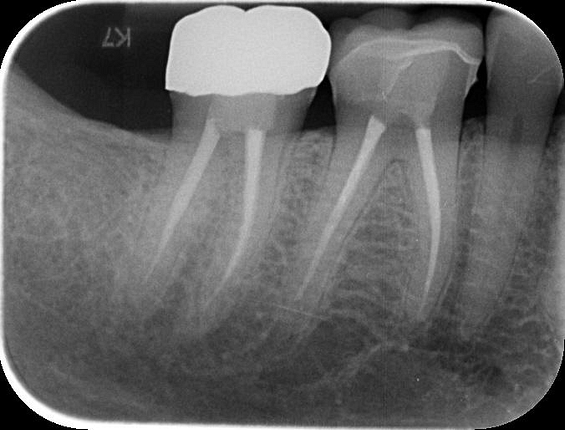

Three months after the implant surgery, a thorough post-operative assessment revealed excellent healing and implant stability.

Digital impressions were captured using the TRIOS 4 intraoral scanner, and the implant-supported crown was designed using 3Shape Design Studio.

At the final appointment, the crown was securely attached to the implant, resulting in a beautiful, natural-looking restoration.

A radiographic assessment confirmed the proper integration and positioning of the implant.